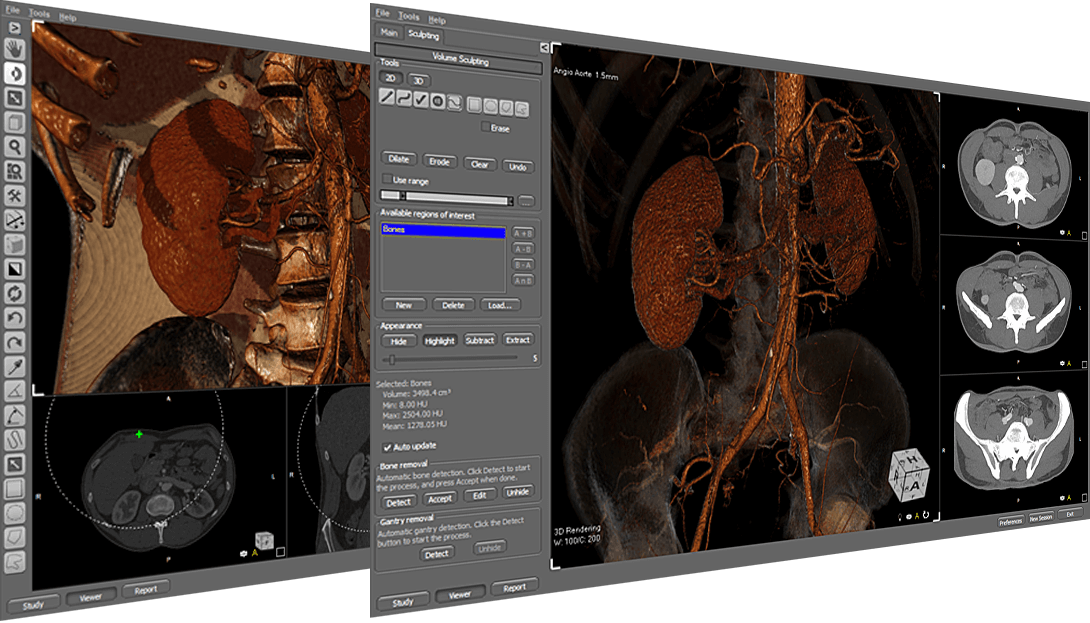

Most DICOM applications today read common imaging modalities like CT, MRI, and ultrasound images. Features such as multiplanar reconstruction (MPR), particularly 3D reconstruction, are needed for treatment planning. Volume rendering, maximum and minimum intensity projections (MIPs) aid in diagnosis as well as in research. Image fusion, such as PET to CTs or PET to MRIs can also help in diagnosis and reporting.

PostDICOM is one of the best DICOM viewers that offers almost all of the above features. It is compatible with Windows, Mac OS X, and Linux. It can be operated from android devices and iOS-based systems. PostDICOM comes with a cloud-based PACS, which allows you to access data from any device, anywhere, at any time. The viewer allows advanced image manipulation, such as 3D reconstruction, 3D volume rendering and MIP, and image fusion. It also offers an interface for creating reports, sharing files, and immediate uploading of all patient data to the cloud PACS.

The Pro Surgical 3D application (from the Stratovan Group) is mainly targeted at surgeons, for surgical planning using their high quality 3D reconstruction feature. However, anyone can use this application to read and understand scans. It has the capacity to anonymize and de-identify patient details in scans, which is a must when the images are used in research, presentations or publications. They have an integrated customer support portal to aid in usage. The application also provides access to the Navegatium Knowledge Base—a comprehensive digital library of medical images.